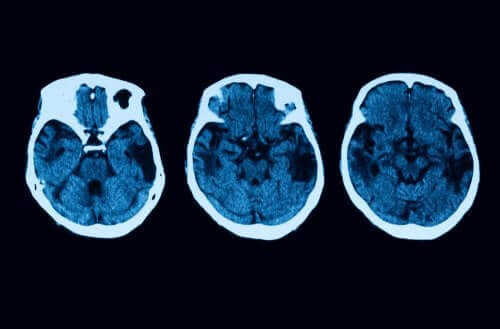

Ces tests pour réaliser un bon diagnostic ne s’arrêtent pas là. Des examens neurologiques, y compris des IRM et des tomographies, sont utilisés pour dissiper tout doute. Si tout indique qu’il s’agit d’un cas d’atrophie corticale postérieure, il existe différents traitements qu’un patient peut choisir.